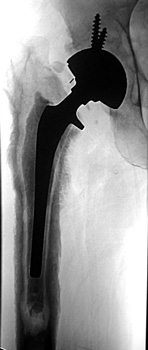

Normal arthrogram